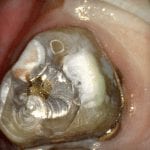

REMAINING TOOTH STRUCTURE AFTER REMOVAL OF PREVIOUS RESTORATION AND PREPARATION REFINEMENT